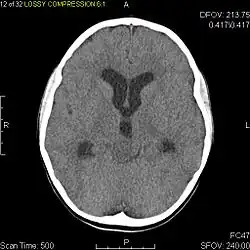

Usually – depending on the interview of the patient and after a clinical exam which includes a neurological exam and an ophthalmological exam – a CT scan and/or an MRI scan will be performed to confirm the presence of a tumor. They are usually easily distinguishable from normal brain structures using these imaging techniques. A special dye may be injected into a vein before these scans to provide contrast and make tumors easier to identify. Pilocytic astrocytomas are typically clearly visible on such scans, but it is often difficult to say based on imaging alone what type of tumor is present.

Pilocytic astrocytomas are often cystic tumors, and, if solid, tend to be well-circumscribed.